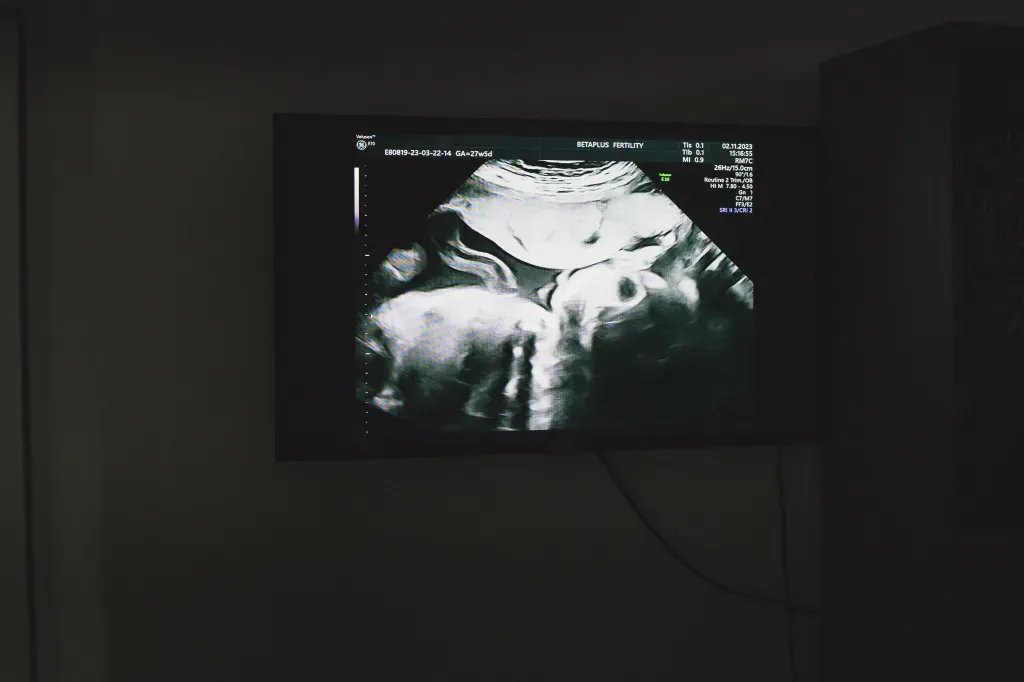

隨後一系列複雜的流程全都由康德利搞定——匹配代理孕母(「代媽」),去公證處簽訂「準父母」(也就是王大哥和他的「女伴」)、捐卵者(「卵妹」)和「代媽」的三方代孕協議。「卵妹」在與康德利合作的輔助生殖診所中促排、取卵,隨後診所實驗室用王大哥的精子和「卵妹」的卵子進行人工授精,形成的胚胎在經過養囊、基因篩查等步驟後,被移植入孕母體內。再過幾周,就能通過B超檢查確定胚胎是否在孕母體內成功着床、是否出現胎心音,一旦有胎心,就意味着妊娠成功,開始進入懷孕管理階段。